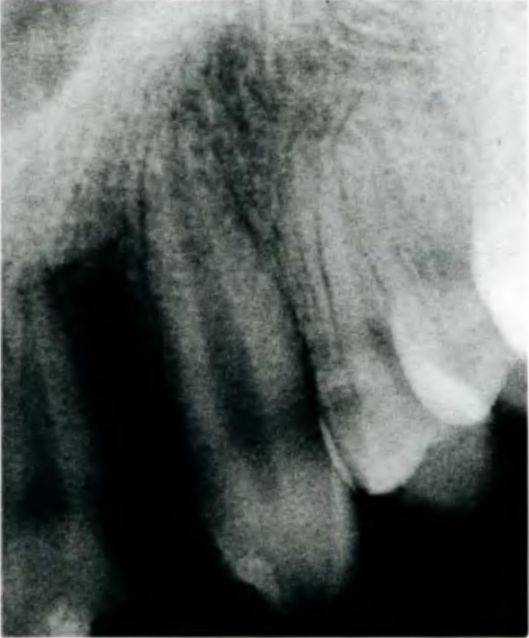

отсутствие бокового резца